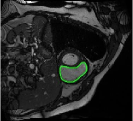

From the above discussions, we have discovered the significant potential of applying Retinex theory to image segmentation and explored its fundamental differences from traditional models. Traditional image segmentation models typically focus on the impact of intensity information on the segmentation results. Therefore, when faced with complex segmentation scenarios, the segmentation results are often affected by lighting, artifacts, and unclear boundaries in the image. As shown in Fig. 1, we present the results of the classical local model LIF [ZHANG20101199] for segmenting brain tumor images along with surrounding tissue edema. The irregular ring-like enhancement caused by the edematous tissue leads to irregular boundaries and low contrast in the images. Consequently, the LIF model can only identify the central necrotic and liquefied regions of the tumor, failing to detect the boundaries and becoming trapped in local minima. In this paper, we draw inspiration from the Retinex theory, which is widely applied in the field of image enhancement. According to Retinex theory, the reflectance component characterizes the intrinsic structural properties of the observed image and preserves texture information independent of illumination variations. By integrating this reflectance component into the level set framework, our model achieves robust segmentation of medical images even under severe intensity inhomogeneity. In addition, a linearized Structural-Prior is proposed to restore intensity consistency and capture local geometric features, thereby improving boundary localization in complex or blurred regions. Furthermore, a relaxed binary level set representation is employed to enhance robustness against noise and to enable accurate tracking of complex contours. Based on these innovations, we propose a novel variational reflectance-based level set model (RefLSM) that simultaneously corrects bias fields and performs segmentation. Experimental results demonstrate that RefLSM significantly outperforms conventional level set methods in both segmentation accuracy and robustness. We present the results of our model segmenting the two brain tumor images mentioned above in Fig. 2.

To address the challenge of segmenting images with severe intensity inhomogeneity, we propose a linearized structural prior that directly operates on the reflectance component . Reflectance-based structural information is more robust to illumination variations and bias field distortions, helping preserve weak edges and subtle anatomical boundaries. As shown in Fig. 2, our method can accurately delineate tumor boundaries and surrounding edema even under severe inhomogeneity, where traditional intensity-based models often fail. The proposed prior aligns smoothed reflectance gradients with data-driven directions, enhancing inter-region contrast, preserving weak edges, and stabilizing the evolution of . Formally, we define the linear structure operator as the gradient field of the smoothed reflectance: